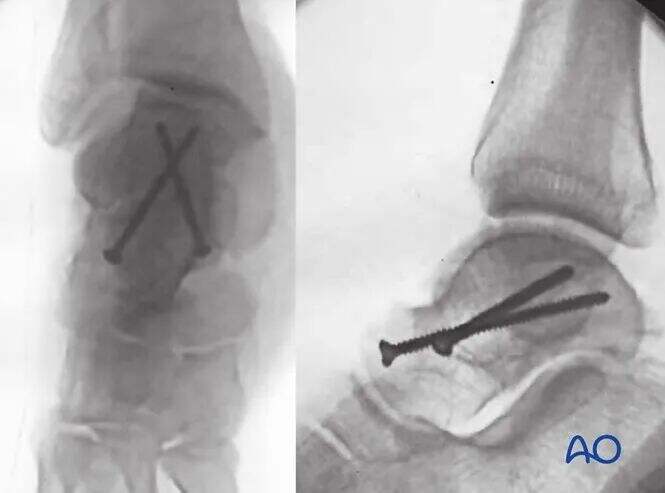

Intraoperativni pregledi s C-armom zagotavljajo natančno redukcijo vseh sklepnih površin talusa. Canalejevi posnetki gležnja in stopala potrjujejo zadovoljivo redukcijo in fiksacijo fraktur vratu talusa.

Ilustracija prikazuje stabilno fiksacijo zloma tipa Hawkins II. Obravnavajte nevzporedno postavitev vijakov: kompresijski vijak lateralno in pozicijski vijak medialno.